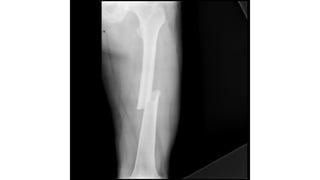

This document discusses femoral fractures, categorized by their location and severity, with classifications such as Garden classification. It outlines the types of fractures, including valgus impacted, non-displaced, partially displaced, and fully displaced, along with their surgical treatment options. Additionally, it briefly describes distal femur fractures, which occur just above the knee joint.